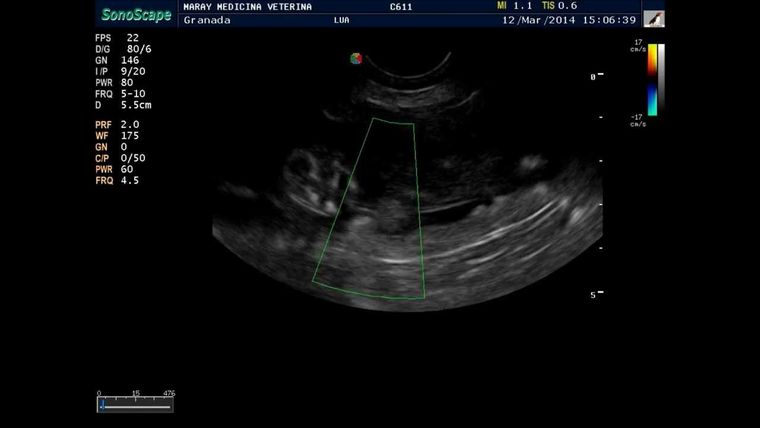

En diálogo con MDZ Napsix, el veterinario Agustín Carbone aportó las imágenes de la ecografía a una perra que había estado en celo hace unos dos meses aproximadamente. Se encontraba decaída y con la panza muy hinchada, por lo que el médico veterinario dispuso realizarle los análisis con urgencia para evaluar las causas del malestar del animal. De paso, Carbone aprovechó para recordar que la salud de las mascotas depende de los análisis que les hagamos con frecuencia.

Al hacer referencia al examen practicado, Carbone dijo: "El contenido del útero se ve con una colecta que puede ser sangre o pus, a medida que me desplazo hacia la cabeza se ven con mayor nitidez los cuernos del útero con contenido, lo cual no es normal. En ninguna ecografía que aparezcan ese tipo de rastros puede hablarse de un animal sano. En este caso esta perra tiene una colecta enorme, y necesita ser operada de modo urgente".

Mascotas: así se ve una ecografía a una perra